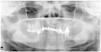

Two cases of oral pulse granuloma (OPG) or vegetable granuloma (VG) are presented, one of which was concomitant with an odontogenic keratocyst (OKC), which is an unusual finding. OKC is characterized by the presence of hyaline rings which include vessels, giant cells, other inflammatory cells and collagen fibres. There are two hypotheses as to its histogenesis: firstly, as a reaction to vegetable matter, such as legumes (thus the nomenclature “pulse” or edible seed) and secondly as a degenerative change in the vessel walls as a result of localized vasculitis.

Due to the deceptive appearance of OPG, diagnosis can be challenging.